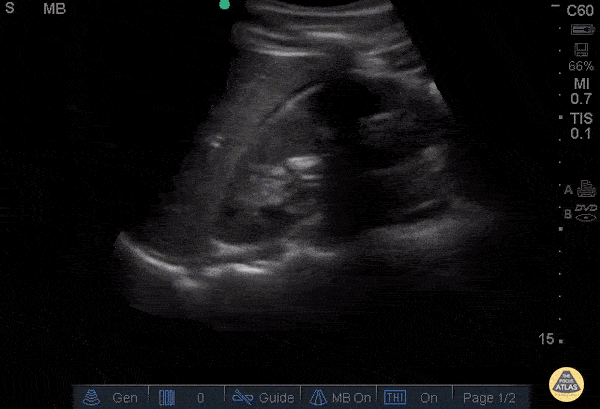

Trauma - Positive FAST - RUQ

30 y/o pedestrian struck by car, hemodynamically unstable, tachycardic. FAST performed after primary survey revealed free fluid in all four abdominal views of the FAST exam Free fluid in Morison’s pouch of the RUQ view. This is the most sensitive view to detect free fluid in trauma. Dr. Catharine Bon - Kings County Emergency Medicine